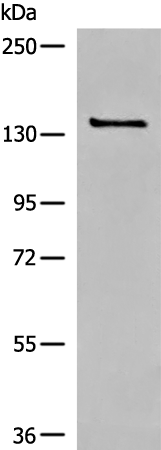

分类: 科研抗体货号: P05898别名: MKS12应用: WB,IHC反应种属: Human